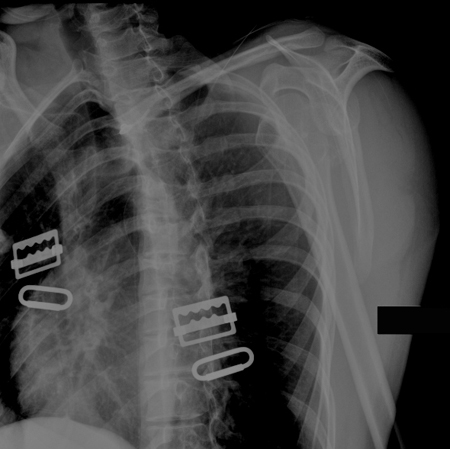

Incidência anteroposterior de radiografia de luxação do cotovelo

Acervo pessoal do Dr. Paul Novakovich